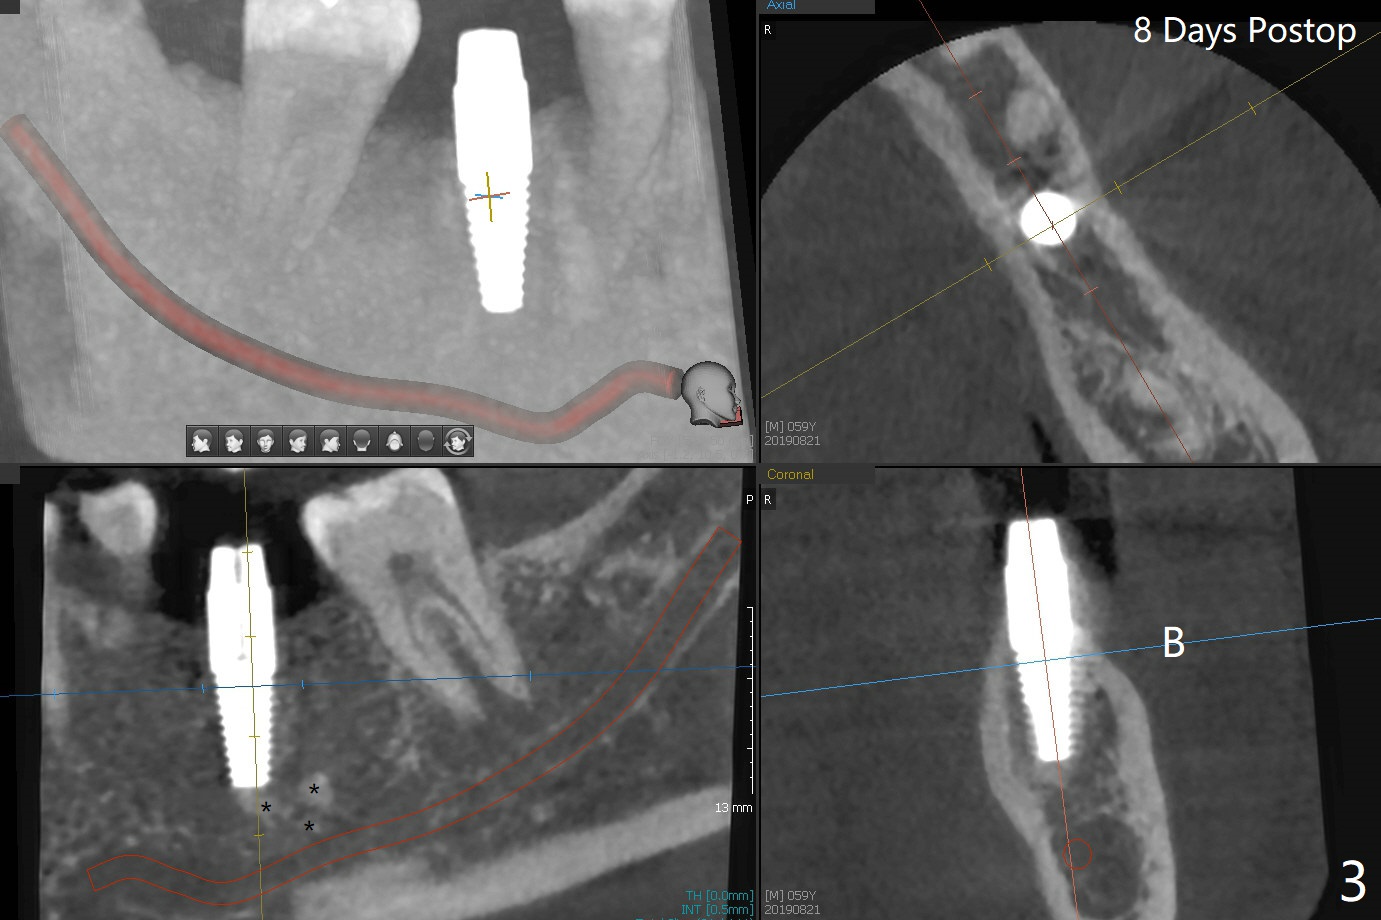

After 4.0x10 mm drill with 9 mm offset for 4.5x10 mm bone-level implant at #19, a 4.5x17 mm tissue level tap is inserted with apparently low torque (probably without reaching the depth). When a 4.5x14 mm tissue level implant is placed with high torque, a 4.5x7.3 mm drill is used for ~ 6.5 mm. The implant loses the primary stability with over-insertion (Fig.1). When an abutment is placed, the implant is critically loose. Mixture of autogenous bone, Osteogen and allograft is placed in the osteotomy. The implant regains stability with better placement level for restoration (Fig.2). In fact the bone density around the implant increases (Fig.2 *). For the first 7 days postop, the patient has to take Advil. When he returns for follow up 8 days postop (Fig.3), the pain decreases, while there is minor degree of lower lip paresthesia. Medrol Dose Pak and Tylenol III are prescribed. The implant is loose 24 days postop; after removal of the implant and apparently infected bone graft, a 7x14 mm dummy implant is inserted with <20 Ncm and 3-4 mm clearance (Fig.4). A longer dummy implant seems to improve stability (Fig.5). So does the definitive implant (Fig.6,7, 25 Ncm), but it is placed low. The gingiva looks healthy 13 days postop (2nd placement). A healing cap will be placed for restoration ~ 3 months postop. CT will be taken if the implant needs to be backed up to determine whether there is enough bone buccolingually. Due to coronavirus and prolonged placement of a healing abutment with poor oral hygiene, the buccal gingiva of the implant is erythematous 1 year postop (Fig.8 healing cap just removed) with bone loss (Fig.9,10 *). Sticky bone seems to be necessary. A 6x5 mm abutment with slots will be placed to hold periodontal dressing in place.